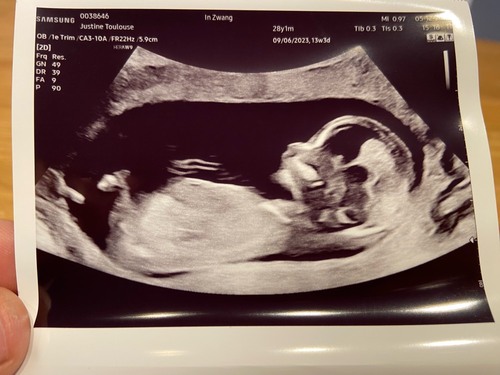

Vrijdag geslachtbepaling! Maar even kijken wat jullie denken 😉 foto is 13+3